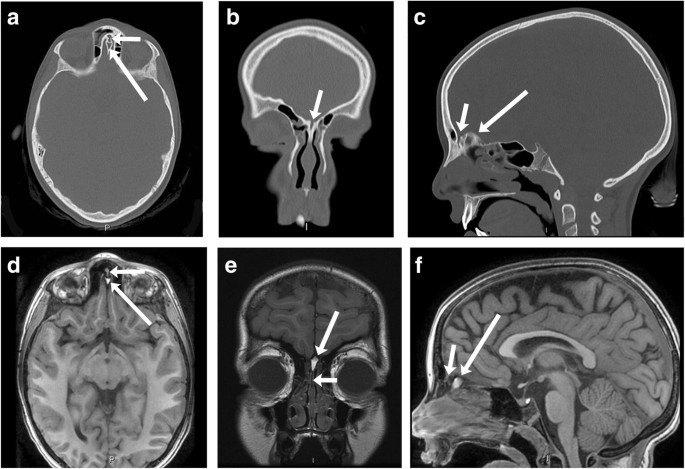

Dermoid cysts are rare lesions of the head and neck that usually present in children as an asymptomatic slowly growing mass. Dermoid is playable in. Words used to describe the skin - thesaurus.

Meet In The Middle A Technique For Resecting Nasocranial Dermoids Technical Note And Review Of The Literature Springerlink